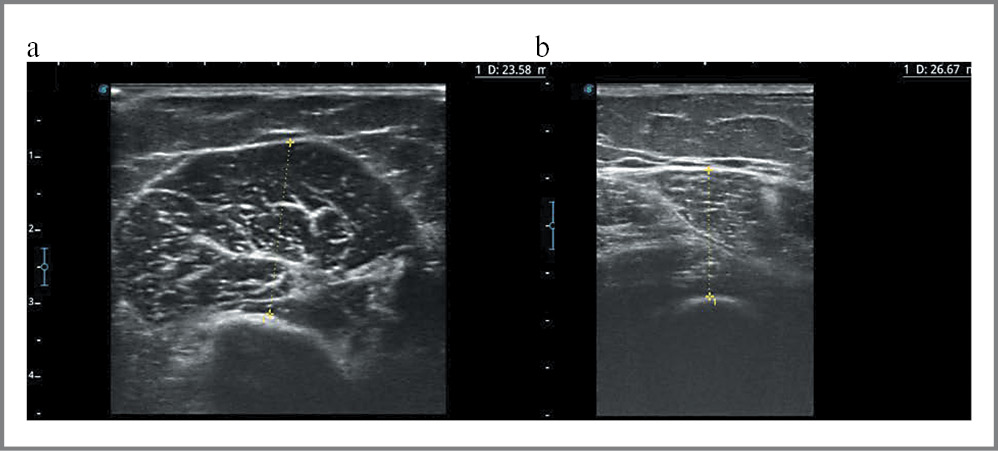

УЗИ мышц проводилось с помощью прибора Sonoscape S2N линейным датчиком с частотой 4–16 МГц. Датчик устанавливался перпендикулярно ткани, под углом 90° относительно костных ориентиров. Степень давления на ткани являлась минимальной. Проведен анализ ультразвуковых толщин мышц плеча (УЗ-СП) и бедра (УЗ-СБ). УЗ-СП определена толщиной musculus biceps brachii (рис. 1, а), оценена в точке 50% на участке, измеряемом от передней части акромиона до локтевого сгиба, в котором можно пропальпировать сухожилие. УЗ-СБ оценена толщиной musculus quadriceps femoris (рис. 1, b) – в точке 50% на участке, измеряемом от большого вертела бедра до проксимальной части надколенника [10].

Рис. 1. Ультразвуковое измерение толщины мышц плеча (a), бедра (b). Эхограммы из личного архива авторов.

Fig. 1. Ultrasonic measurement of the thickness of the muscles of the shoulder (a), thigh (b). Ultrasonograms from the authors' personal archive.